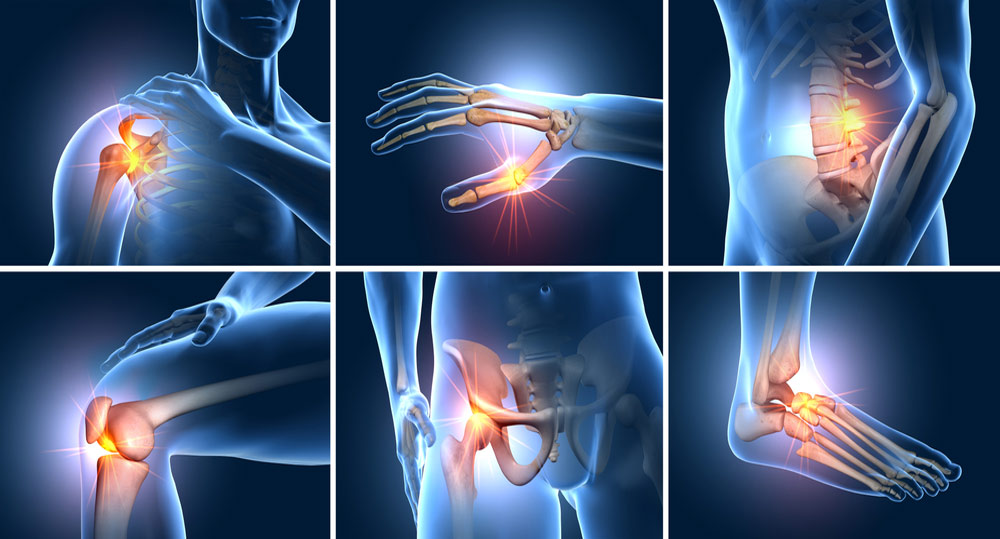

Musculoskeletal pain, and joint pains, are devastating and paralyze normal life. Orthopedics helps you heal and have a normal life, treating and managing your pain. Orthopedic surgery or orthopedics is the branch of surgery concerned with musculoskeletal system conditions. Orthopedic surgeons use both surgical and nonsurgical means to treat musculoskeletal trauma, spine diseases, sports injuries, degenerative diseases, infections, tumors, and congenital disorders. From pain management, and critical orthopedic surgery to rehabilitation we got you covered at every point of life that is pain-free.